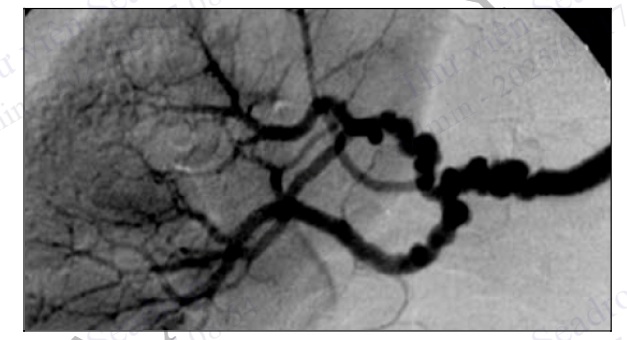

Hình 4.95. Chụp ĐMV trái ở tư thế chếch đầu 30° cho thấy hẹp khít 90% đoạn giữa động mạch liên thất

Hình 4.96. Chụp ĐMV trái sau can thiệp đặt stent ĐM liên thất trước cho thấy lòng mạch bị hẹp đã được tái thông